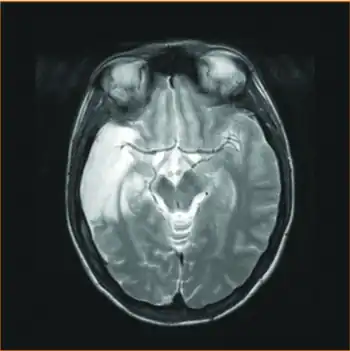

| MRI sequence - injury was sustained before PFO closure, most probably due to paradoxical embolism after documented deep venous thrombosis | |